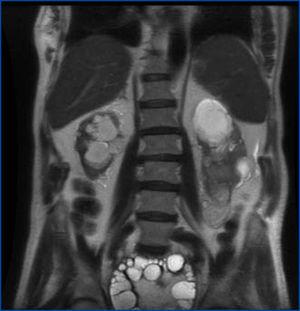

La resonancia magnética (figura 1) muestra una gran lesión ocupante de espacio de 17,5 cm de diámetro máximo que invade la cavidad pélvica con el polo superior a la altura de L4-L5, ejerciendo un colapso casi total de la vejiga. Tiene forma ovoidea, bien definida, con múltiples septos internos, compatible con quiste hidatídico tipo II2B de Polat. En polo inferior del RI se observa una lesión de 61 mm ovoidea compatible con quiste hidatídico inactivo tipo III. Hay dilatación de ambos sistemas colectores renales, con disminución del RD, que tiene un diámetro de 84 mm y cortical adelgazada. El RI tiene un diámetro longitudinal de 11 cm.

Figura 1. Resonancia magnética